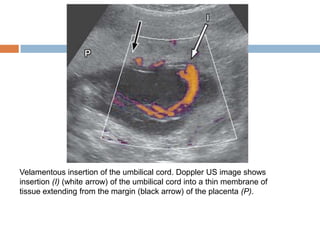

Velamentous insertion of the umbilical cord. Doppler US image shows

insertion (I) (white arrow) of the umbilical cord into a thin membrane of

tissue extending from the margin (black arrow) of the placenta (P).

The umbilical cord typically inserts centrally, but eccentric and velamentous (outside the placental margin) insertions also occur .  Eccentric insertions are cord insertions that are less than 1 cm from the placental edge. These are distinguished from a velamentous insertion, where the umbilical cord inserts on the chorioamniotic membranes rather than on the placental mass. This membranous insertion results in a variable segment of the umbilical vessels running between the amnion and the chorion, unprotected by Wharton jelly

Velamentous insertion ofthe umbilical cord. Doppler US image shows insertion (I) (white arrow) of the umbilical cord into a thin membrane of tissue extending from the margin (black arrow) of the placenta (P).